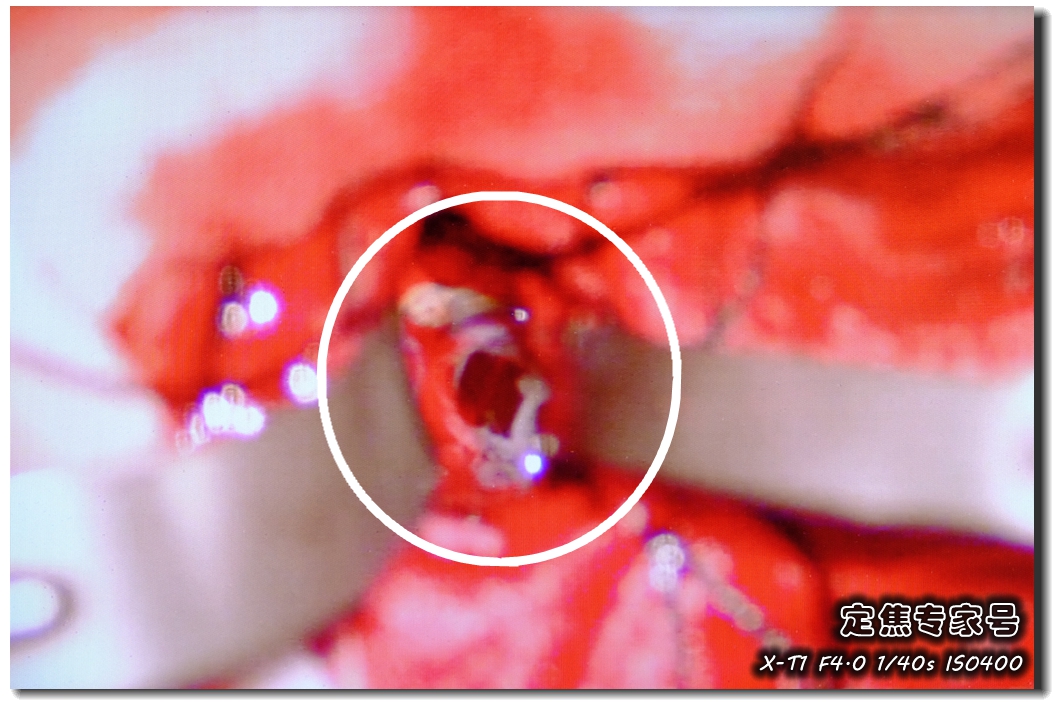

五天之后,吴斌教授为蓉蓉做了开颅手术。这是肿瘤破皮儿之后的样子,里面是一泡水样的液体,把液体吸走,皮儿清理干净。在瘤子周围是错综复杂的神经和血管,一个手抖都会造成不可逆的伤害,这对于专业知识专业技术都是过硬的要求。三个小时之后,蓉蓉脑子里这个几乎有荔枝那么大的肿瘤,被消灭。